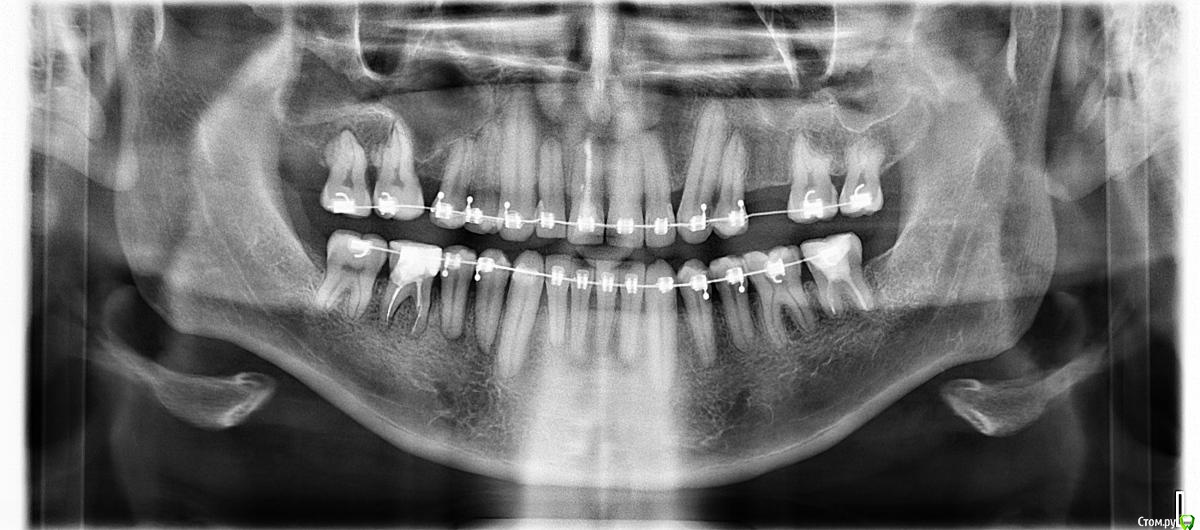

Nick-ev Опубликовано 26 ноября, 2018 Поделиться Опубликовано 26 ноября, 2018 Ношу брекеты уже больше 5ти лет!!!!!!! Очень сильно начали портится зубы, хочу срочно снимать.Вопрос только по правому резцу, он расположен выше левого (не симметрично) врач утверждает, что зуб сточен и опускать его нельзя. Но я то отлично помню, что он поднял его т.к. в него упирался нижний клык, клык давно ушел назад и ничего не мешает выровнять резец. За столько лет я уже не верю никому, но кариес под брекетами дело серьезное. Вопрос, стоит ли выравнивать резец и сколько времени это займет?Было в 13 годуСтало в 18 году Ссылка на комментарий